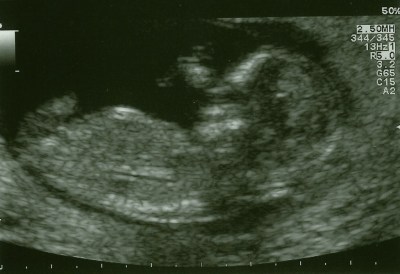

I was called in for my scan on time (what’s going on, that never happens, like ever!) and was told it was going to be conducted by a trainee. ‘Oh great’ I thought. My last scan on my little girl was conducted by a trainee and she died a few days later. I’m not saying there’s a link, but maybe they pressed too hard, or didn’t pick up on something they should have? I will never know. Anyway this lady asked me to sit on the bed while they looked through my notes, they openly discussed them until the senior sonographer called the trainee over to the corner and pointed at a bit of my notes and I heard her whisper late term and then something about sensitive. I can only assume they had got to the part of the notes that told them about my miscarriage early last year. This bugged me, why did she need to whisper as if to keep me out, I do know about it, it happened to me! The trainee came back, lay me down, put the jelly on and proceeded with the scan. Initially as the baby came in to view on the screen all I could see was the shape, I stared and stared trying to see some heart movement, which the trainee quickly told me ‘so there’s baby with a nice heartbeat’ relief washed over me from my moment of panic and a few seconds later Shrimp had thrown their hand above their head as if to wave hello! There was a lot of wiggling of arms and legs, and hiccuping, until they tried to get the length measurement at which point shrimp rolled on their side and fell asleep. Fantastic! They tried every which way to position the scanner so they could measure the length, but eventually asked me to roll on my side, and then back onto my back to see if this had shifted baby’s position! I did offer to stand up and jump around, they didn’t take me up on it, though I’m pretty sure it would have been easier if they had. After three more ‘just roll on your side’ they decided they had the best angle they were going to get and proceeded with the measurements. Shrimp was 66.3mm head to rump which they said put me at 13 weeks (5days more than they told me I was at the 8 week scan) and that this made my due date 8th August. After requesting a couple of pictures we went back to the waiting room to wait to see the consultant.

Having my blood taken was the most relaxing part of my morning, and that’s saying something! I had a lovely conversation with the lady and, following normal routine, I looked solidly at everything else but the needle stuck in my arm. After this we headed back to the ultrasound reception hopeful, if nothing else they’d have been able to photocopy the one they had, however the lady who had done my scan had only just come out and they went to see what they could do. I was sent off to wait, yet again and about 5 minutes later was called back and given a second picture which I was told unfortunately the only one they had saved was the one with the measuring line on, though she assured me you could hardly see it… (I disagree) Thankfully the receptionist was lovely and gave us one of the tokens back to use next time, hopefully we don’t lose it before then!!